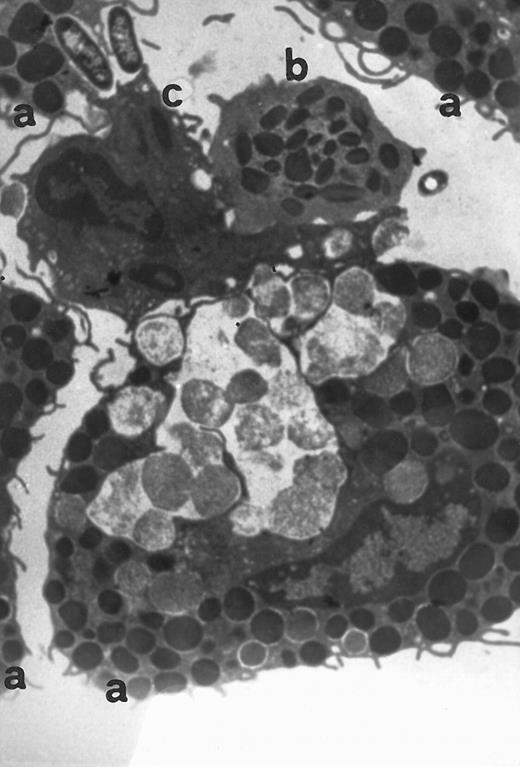

Electron microscopy of skin injection sites.To better analyze the skin injection sites exposed to RANTES, an electron microscopic study was performed. Here we show a representative experiment of four (Fig 4). This electron micrograph (×13,800) depicts accumulation of four basophilic cells (a), one eosinophil (b), and a macrophage (c), 4 hours from injection, with a pattern describing a typical inflammatory event and showing chemoattraction activities toward several cell types.

Transmission electromicrography of a representative experiment of rat inflamed injection site produced by RANTES 10 ng. The section showing the kinetics of the dermal response to exogenous RANTES 4 hours after injection. Evidence for intravascular activation of basophilic cells (a), eosinophil (b), and macrophage (c). Original magnification × 13,800.